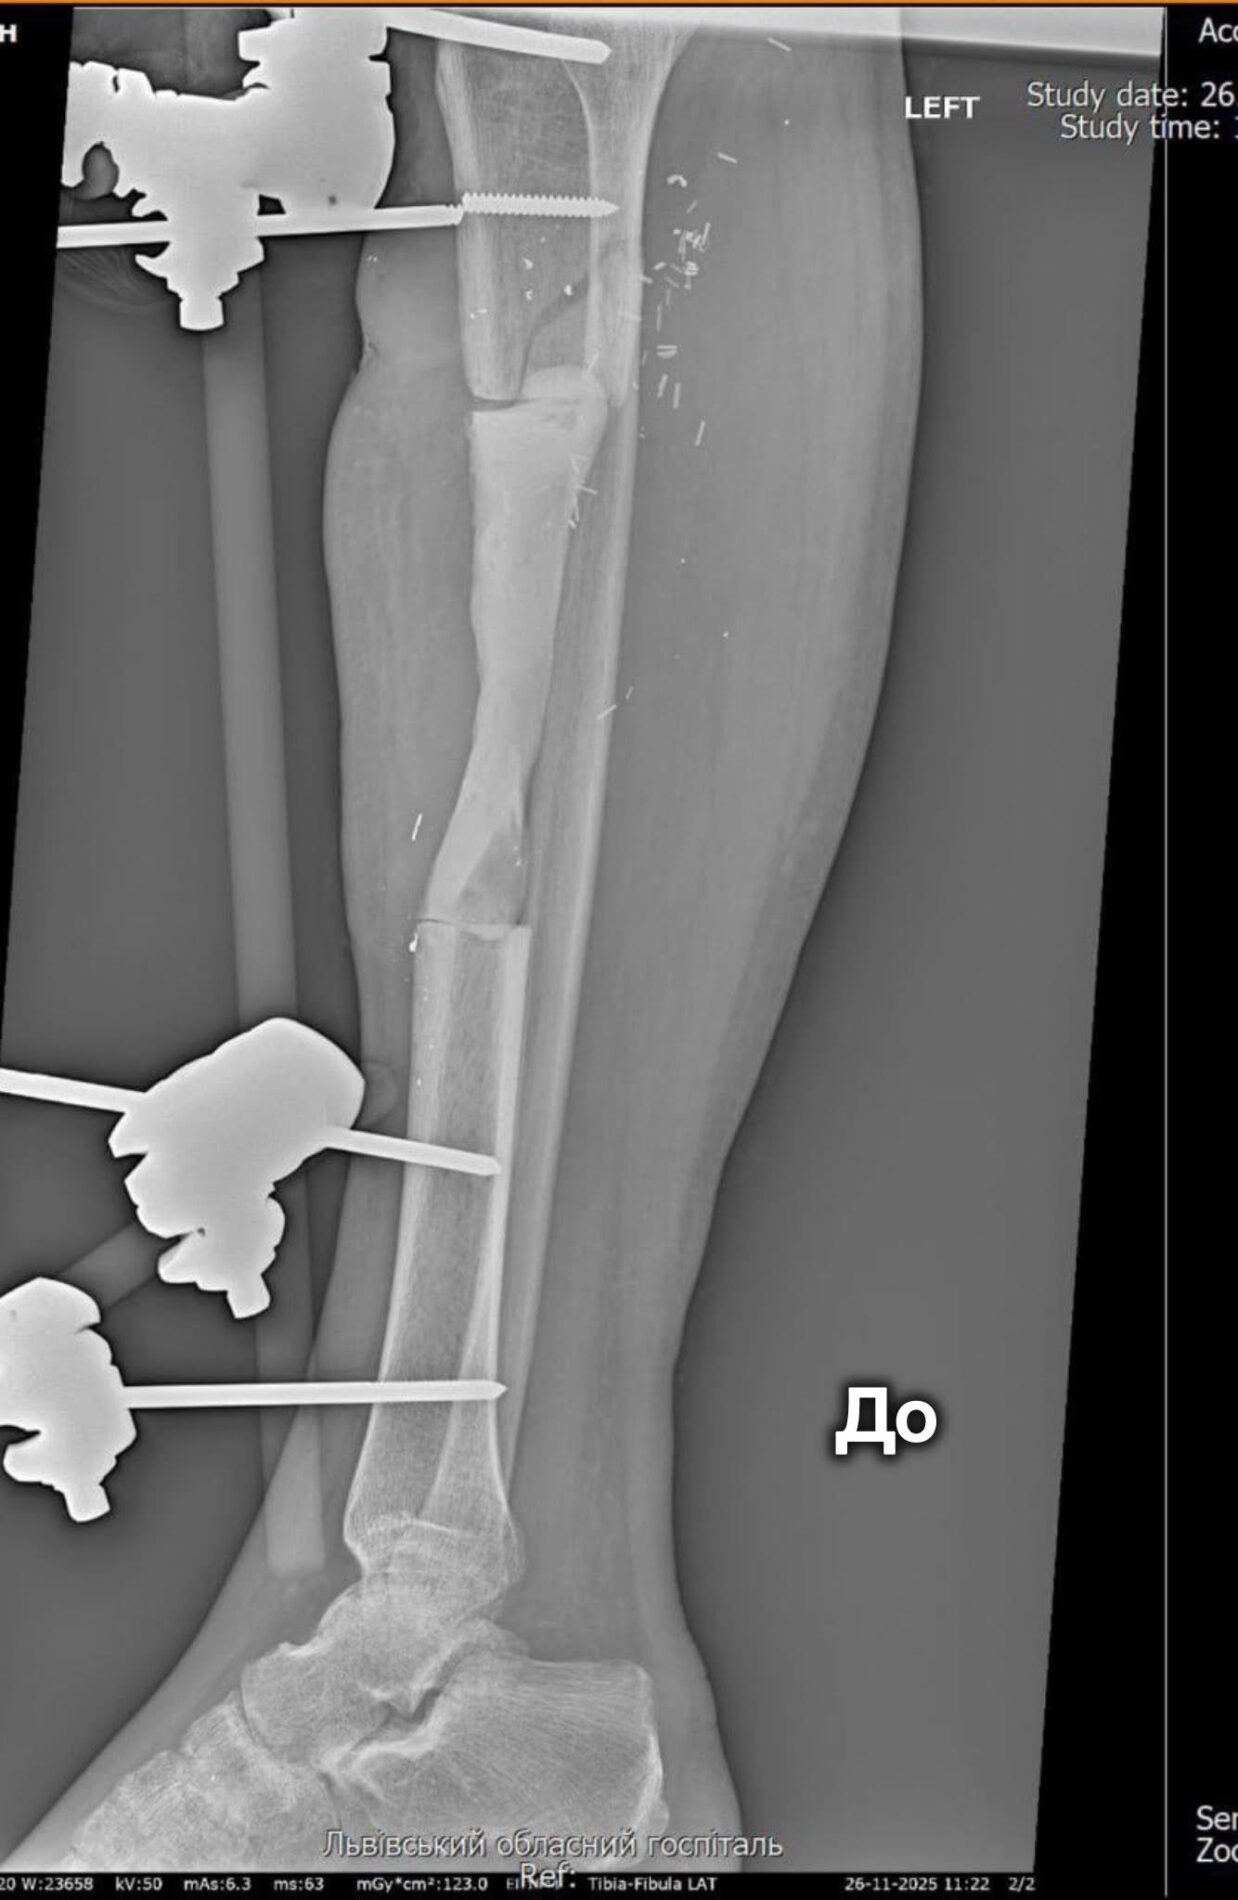

Пацієнтом став військовослужбовець із критичним кістковим дефектом довгої трубчастої кістки розміром 12,5 сантиметра. За таких ушкоджень традиційні методи лікування часто є малоефективними, тож медики ухвалили рішення застосувати сучасну технологію. На першому етапі лікарі сформували спеціальну кісткову камеру, а згодом заповнили її кістковою тканиною та стабілізували уламки.

«Техніку Маскулет нерідко називають «операцією останньої надії», адже вона дає шанс на відновлення у випадках важких вогнепальних поранень і значних кісткових втрат. Метод дозволяє уникнути тривалого використання апаратів зовнішньої фіксації та скорочує шлях пацієнта до повноцінного відновлення», — зазначають у госпіталі ветеранів.